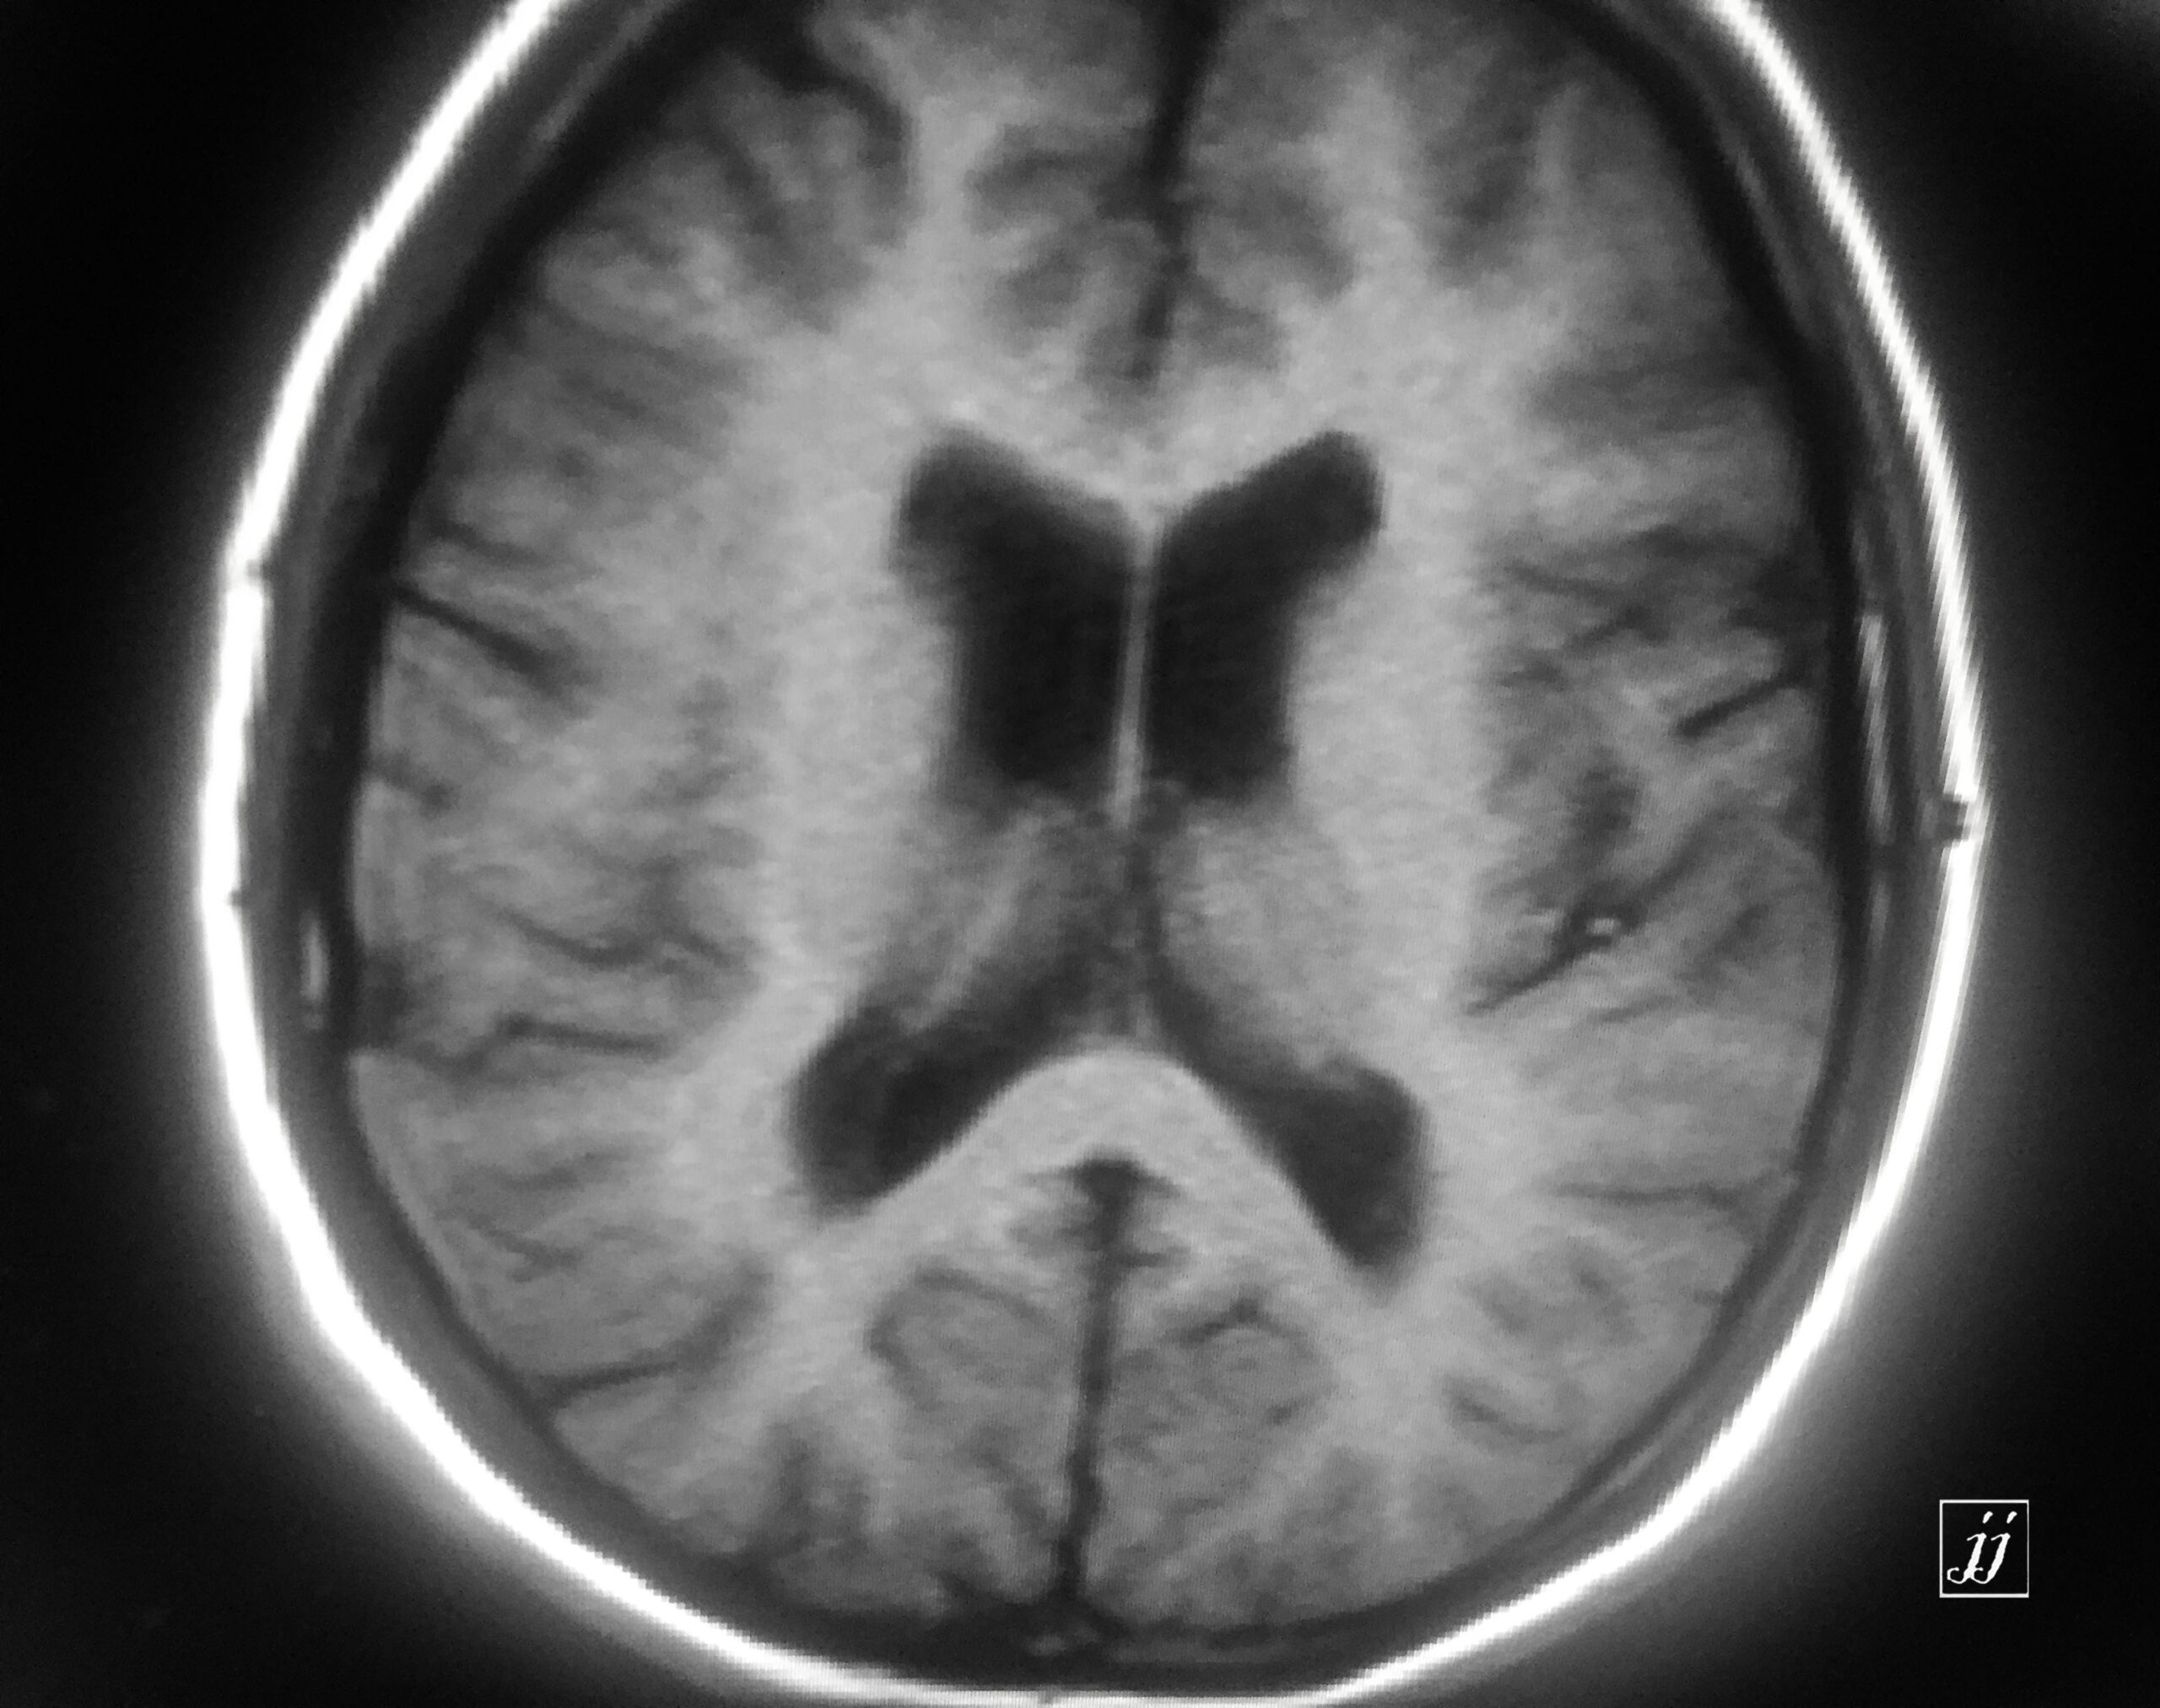

Brain- deep white mater abnormal signal degenerative type (10)